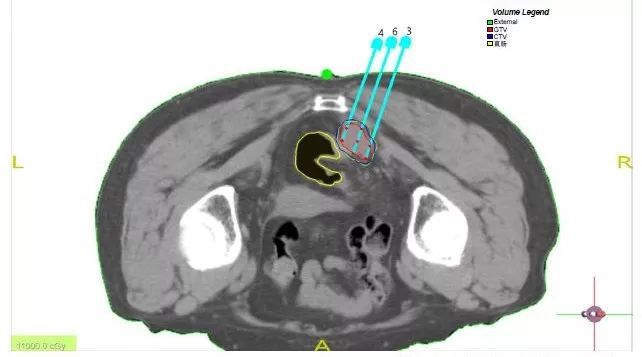

术前TPS计划与手术中进针路径完全相同